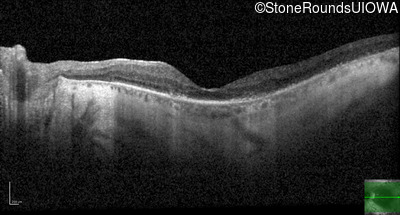

Age at visit: 71 years

This 71 year old man first noticed difficulties seeing in dim light at age 20. He was in the military and recalls needing a flashlight that other service men did not.